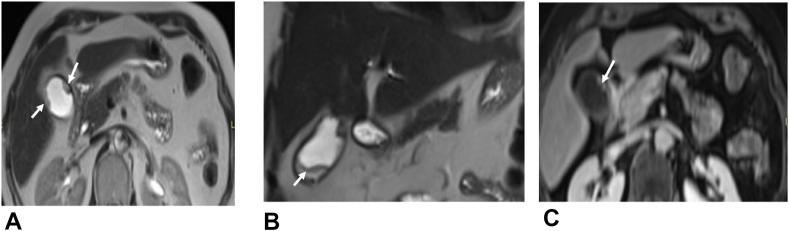

We present a 70-year-old woman, with no family or personal history, who was complaining of pain in the right hypochondrium and an altered general well-being, with no other clinical abnormalities.The imaging including abdominal sonography, CT scan, and MRI concluded at a budding lesion formed in the gallbladder wall which measured 65 × 15mm.Cancer of the gallbladder was suspected and the patient was operated. A resection of segment s4b and 5 of the liver was performed with lymphadenectomy. The post-operative clinical course was uneventful.The diagnosis of cystadenocarcinoma of the gallbladder was confirmed on an anatomopathological exam of the specimen.

我们报告一名70岁女性,无家族史或个人史,主诉右季肋部疼痛且全身状况不佳,无其他临床异常。包括腹部超声、CT扫描和MRI在内的影像学检查发现胆囊壁上有一个大小为65×15mm的芽状病变。怀疑为胆囊癌,患者接受了手术。进行了肝S4b和S5段切除及淋巴结清扫术。术后临床过程平稳。标本的解剖病理学检查证实为胆囊囊腺癌。